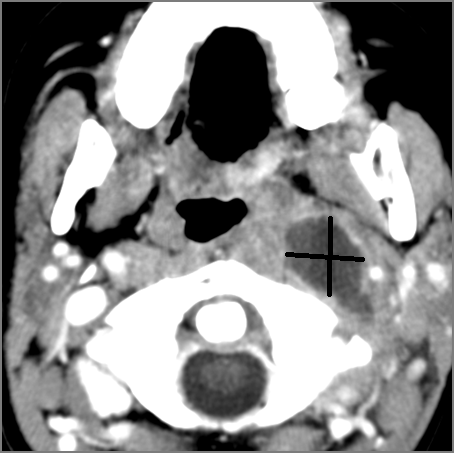

Vascular Findings

There is evidence of thrombus, thrombophlebitis or other occlusive or inflammatory process of the jugular vein or smaller jugular venous tributaries. [Yes/No]

There is evidence of thrombus, inflammation of the common, external or internal carotid artery. [Yes/No]